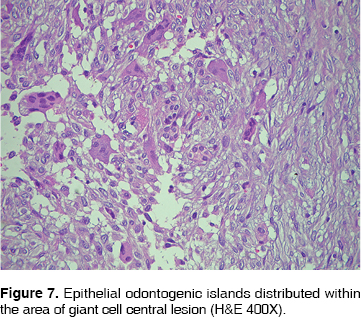

Histological features: the tumor was conformed by fibro-cellular tissue vascularized forming cross linked bundles of fusiform cells with scarce production of collagen, between them islands and strands of non active odontogenic epithelium were found. In some zones specially in the outer area, there was a highly vascularized fibro-cellular tissue where could be found many osteoclastic giant multinucleated cells type, distributed around vessels and some intralesional hemorrhages (Figures 6 and 7).

The case here reported histologically is formed by fibro-cellular tissue well vascularized forming cross linked bundles of fusiform cells and scarce production of collagen fibers, abundant strings and islands of inactive odontogenic epithelium. In some areas of the fibro-cellular tissue many giant multinucleated osteoclast type cells may be identified specially around the blood vessels and intralesional hemorrhage zones. These findings are similar to those described in the previously reported cases.